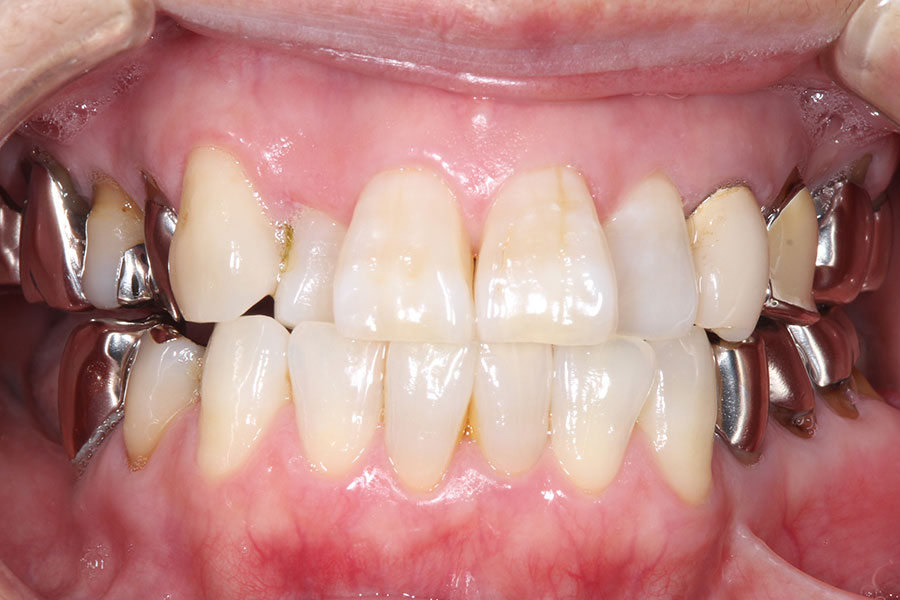

Before -正面-

After -正面-

| 施術内容 | 金属アレルギー予防を目的に、金属フリーの自費補綴へ変更。適合性・清掃性・審美性の向上が得られています。 |

|---|---|

| 治療期間 | 約4ヶ月 |

| 費用 | ハイブリットクラウン ハイブリットインレー 693,000円 |

| リスク・副作用 | 治療にともない、歯の破折や歯質の削合、場合によっては抜歯が必要となることがあります。また、金属や補綴物を除去する際に、完全に除去できない場合もあります。 |